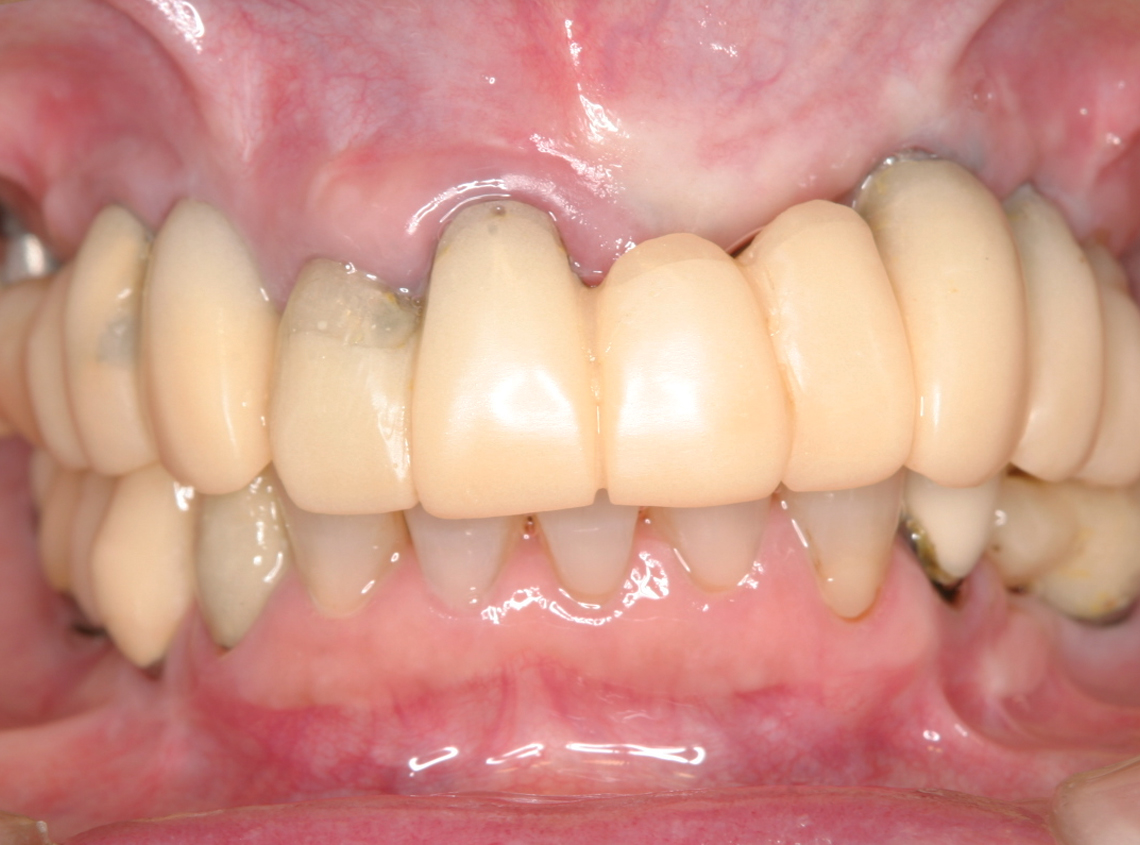

3.治療中の仮歯(2007年)

インプラント埋入終了

4.最終補綴物装着(2008年)